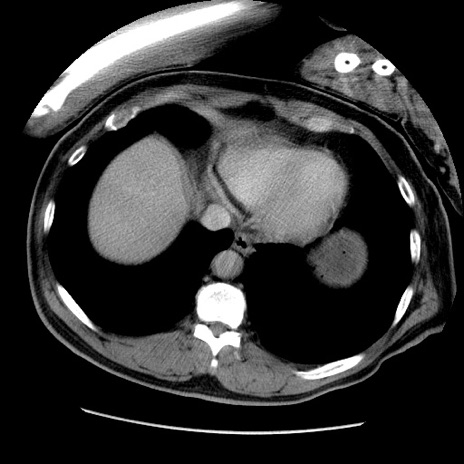

冠状断像

【症例】50歳代男性

【主訴】腹痛

【現病歴】AVMからの被殻出血のため回復期リハ病棟入院中。 本日午後3時頃急に下腹部痛が出現した。

【既往歴】AVM、被殻出血、虫垂炎、高血圧

【身体所見】意識晴明、左半身不全麻痺、会話の理解は良好、36.5°C、腹部:膨隆、全体に板状硬、下腹部正中に圧痛点あり、反跳痛-、筋性防御不明、右下腹部にope scar

【データ】WBC 9400、CRP 0.06